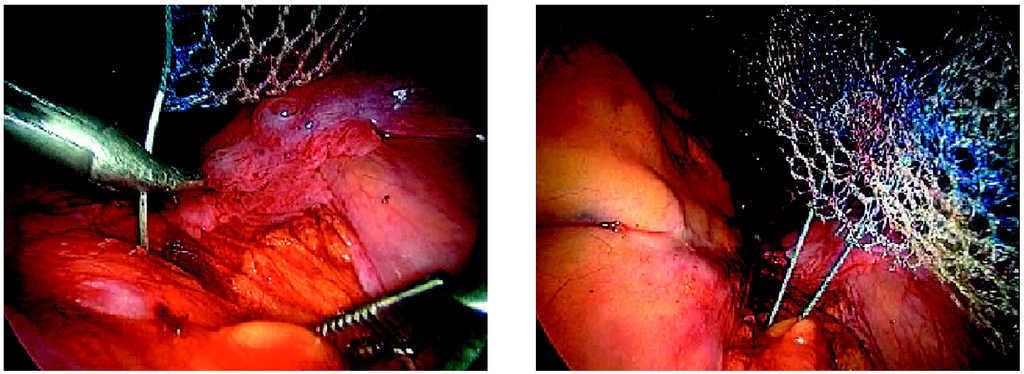

-- Paso tercero. Fijación de la malla de polipropileno a la cúpula vaginal con puntos de sutura no reabsorbible e introducción en cavidad abdominal de la malla y cierre de la cúpula con puntos de sutura aplicados por vía vaginal (fig. 3).

Figura 3.Detalle de la fijación de la malla a la vagina.

-- Paso segundo. Fijación de la malla al promontorio del sacro por medio de grapas helicoidales, tipo táquer, o con puntos endoscópicos de sutura no reabsorbible (fig. 5).

Figura 5.Detalle de la fijación de la malla al promontorio.

-- Paso tercero. Peritonización con puntos sueltos (figs. 6 y 7).

Figuras 6 y 7.Detalle de la peritonización final de la malla.